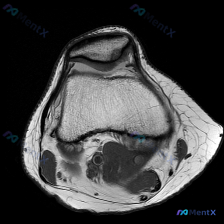

给大家分享一份最近遇到的踝关节MRI读片病例,初始问题指向软骨异常,整理一下完整的分析思路,一起讨论。 一、病例影像基本信息 这是一份踝关节矢状位T2加权MRI图像,图像质量好,信噪比高,解剖结构清晰,涵盖了胫骨远端、距骨、跟骨、足舟骨、骰骨及部分跖骨基底部,胫距关节、距下关节、窦跗管、跟腱等关键结...

看到这个踝关节MRI的读片讨论,整理了完整的影像信息和分析思路,分享给大家。 一、影像基本信息 这是一张踝关节MRI矢状位T2加权图像,T2序列对液体和软组织水肿显示敏感,以下是具体异常发现: 1. 距下关节及跗骨窦区域:距骨下方、跟骨上方的关节间隙及周围软组织可见弥漫性高信号,提示明显积液或炎性水...

刚看到一份踝关节MRI病例,问题是询问影像上观察到的软骨异常相关发现,整理一下资料和分析思路分享给大家。 病例影像基础信息 这是放射影像-踝关节MRI-T2序列-矢状位,系统评估整体结构如下: 1. 骨与关节:胫距关节间隙正常,关节面轮廓可,距骨穹窿皮质连续,未见明确骨折线或弥漫骨髓水肿;距下关节、...

最近碰到一个很有启发的病例,临床问题是问这张踝关节MRI-T1矢状位影像的观察结果是不是软骨异常,整理一下完整分析思路给大家。 一、影像基本信息 本次仅提供踝关节MRI-T1序列-矢状位单张图像,先把客观阅片结果整理出来: 1. 骨骼结构:胫骨远端、距骨、跟骨、足舟骨及部分楔骨显示清晰,骨皮质连续,...

看到这份踝关节MRI的读片申请,核心问题是排查软骨异常,整理了完整的读片和分析思路分享给大家。 一、影像基本信息 这是一张踝关节MRI轴位T2加权图像,扫描层面为踝关节水平,展示胫骨远端后方、距骨及后踝周围软组织结构: 1. 骨结构:胫骨后缘、距骨体后部轮廓清晰,骨皮质低信号、骨髓中等信号,未见明显...